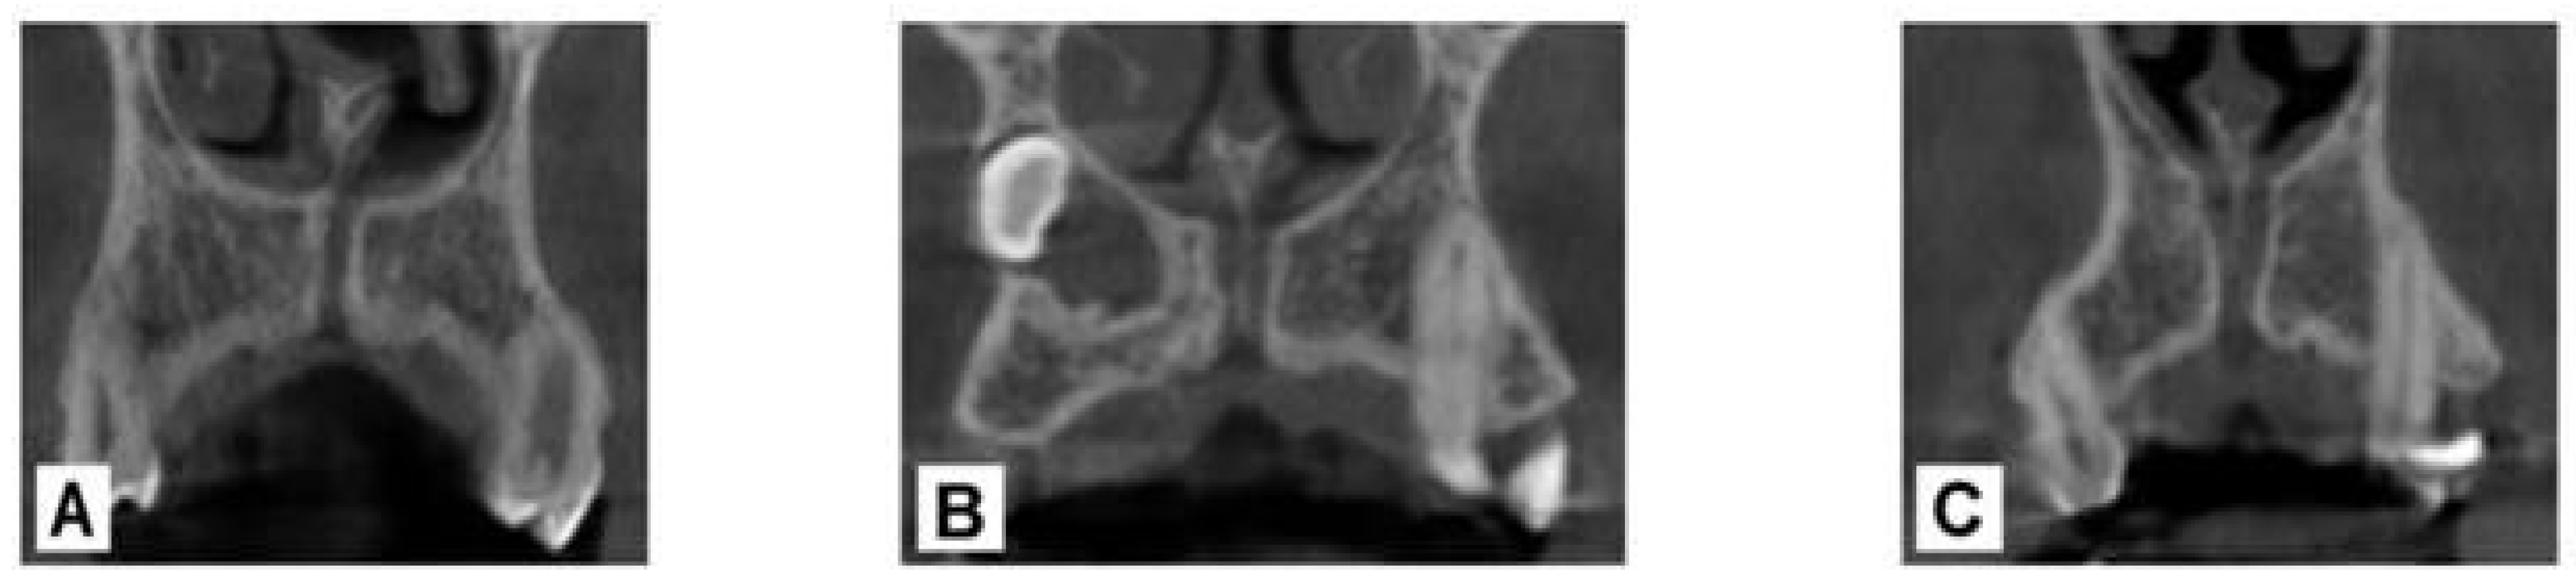

Several studies have reported morphological variations in the NPC in both the coronal and sagittal planes. In the coronal plane, Bornstein et al. classified the NPC into three distinct types: Type ‘a’, single canal; Type ‘b’, double canal; and Type ‘c’, Y-shaped, characterized by a single canal in the coronal portion and bifurcation in the apical portion [7] (Figure 1).

Figure 1. Anatomy of the nasopalatine canal in the coronal plane. (A) single canal, (B) double canal, (C) Y-shaped.